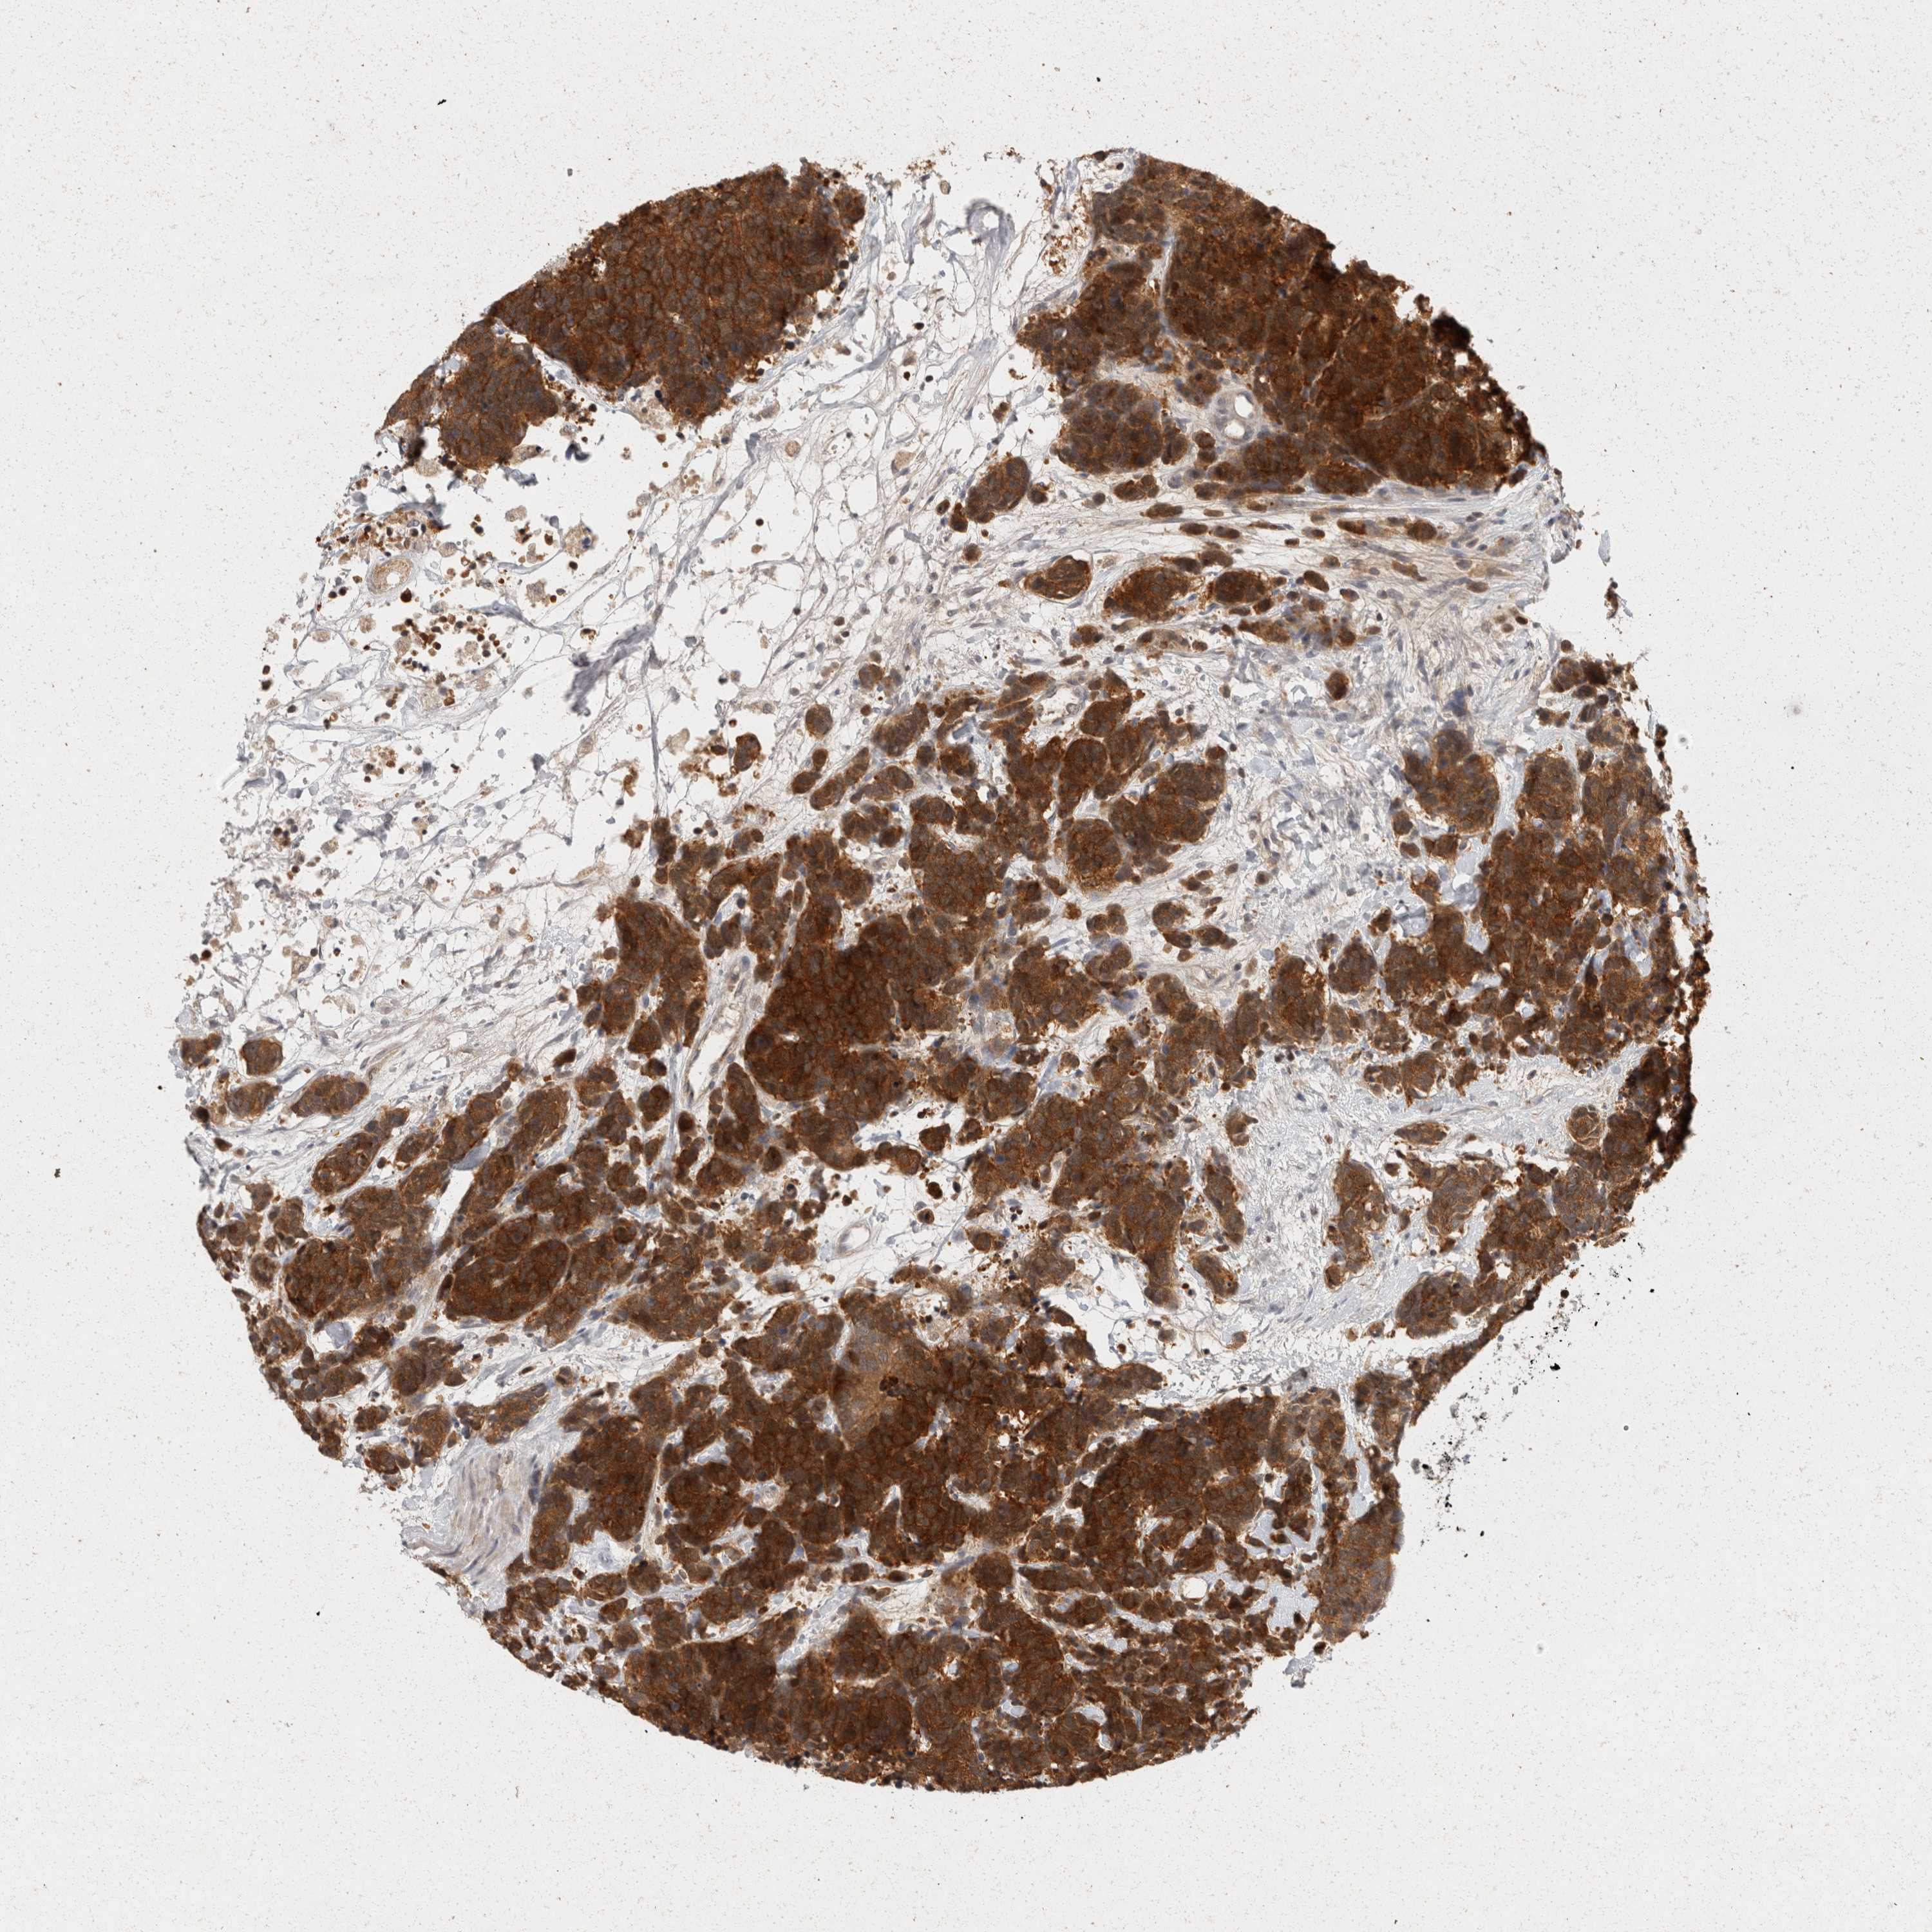

CARCINOID - Protein expressioni

A mouse-over function shows sample information and annotation data. Click on an image to view it in a full screen mode. Samples can be filtered based on level of antibody staining by selecting one or several of the following categories: high, medium, low and not detected. The assay and annotation is described here.

Antibody stainingi

Antibody staining in the annotated cell types in the current human tissue is reported as not detected, low, medium, or high, based on conventional immunohistochemistry profiling in selected tissues. This score is based on the combination of the staining intensity and fraction of stained cells.

Each image is clickable and will lead to virtual microscopy that enables deeper exploration of all samples and also displays staining intensity scores, fraction scores and subcellular localization as well as patient and tissue information for each sample.

Antibody HPA025736

Staining

High

Intensity

Strong

Quantity

>75%

Location

Cytoplasmic/membranous

Carcinoid, malignant, NOS